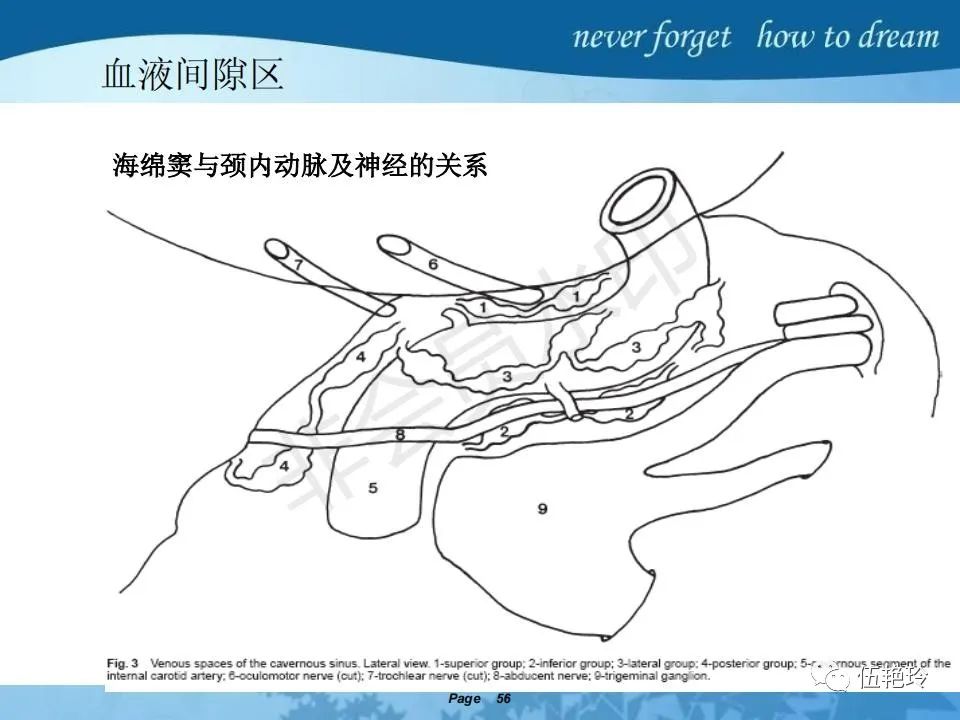

海绵窦区的解剖结构与鼻咽癌侵犯